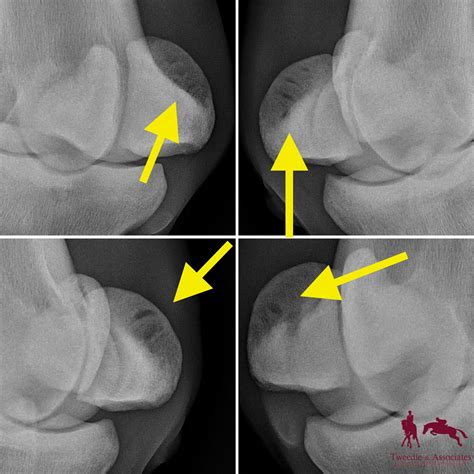

• Physical Examination: A thorough examination of the foot to assess pain, swelling, and range of motion.

• X-Rays: X-ray images to visualize the bones and identify any fractures.

• MRI or CT Scan: Advanced imaging techniques to provide a more detailed view of the sesamoid bones and surrounding tissues.